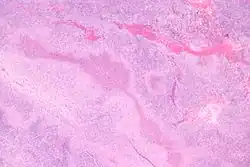

Cat-scratch disease is characterized by granulomatous inflammation on histological examination of the lymph nodes. Under the microscope, the skin lesion demonstrates a circumscribed focus of necrosis, surrounded by histiocytes, often accompanied by multinucleated giant cells, lymphocytes, and eosinophils. The regional lymph nodes demonstrate follicular hyperplasia with central stellate necrosis with neutrophils, surrounded by palisading histiocytes (suppurative granulomas) and sinuses packed with monocytoid B cells, usually without perifollicular and intrafollicular epithelioid cells. This pattern, although typical, is only present in a minority of cases.[16]